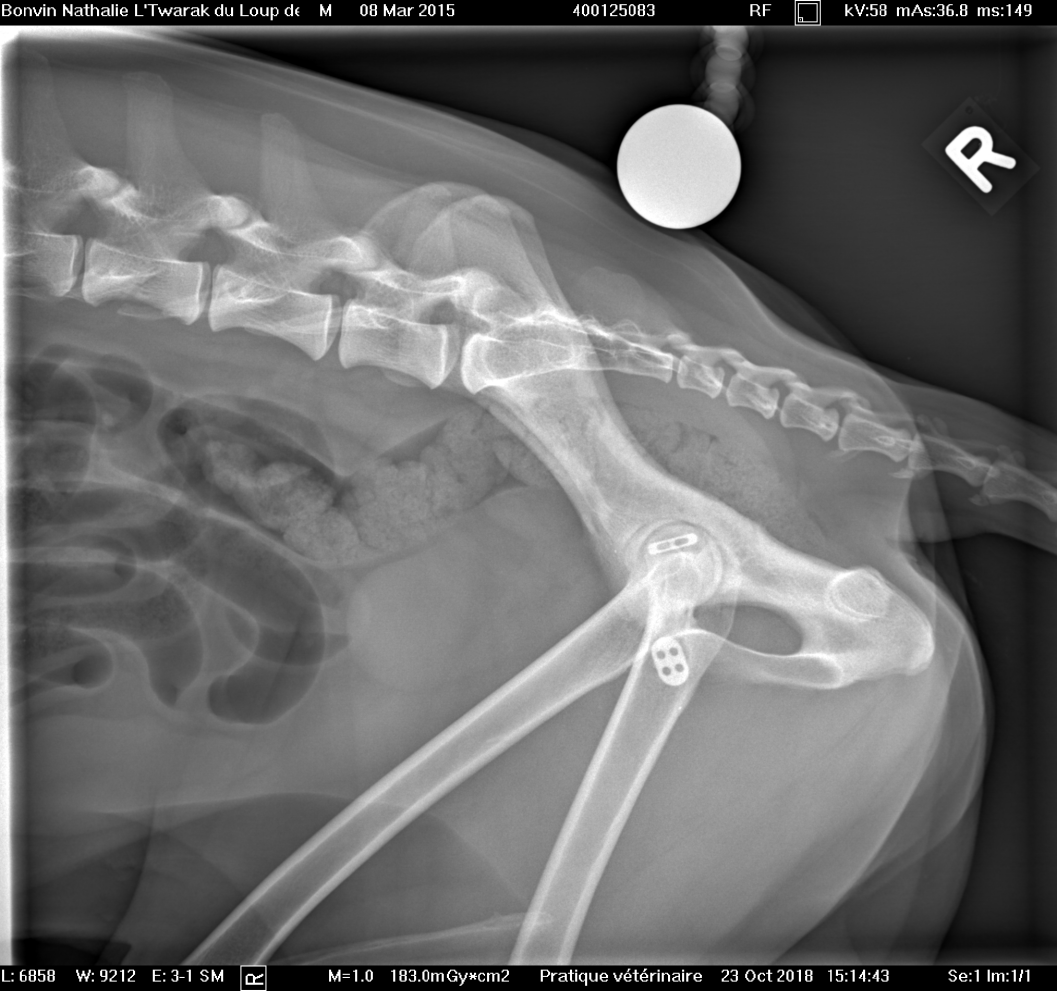

Voici les radios du 23 octobre... la tête du fémur est nécrosée...sur problème infectieux... je ne suis pas contente... la seule alternative qu'il reste maintenant et de tout enlever, de couper la tête du fémur... et Twarak devra vivre ainsi.

Il me dise que pour un chien comme lui, c'est très gérable... je suis triste pour Twarak....

opération et mise en place d'un bouton-clou dans la tête du fémur gauche